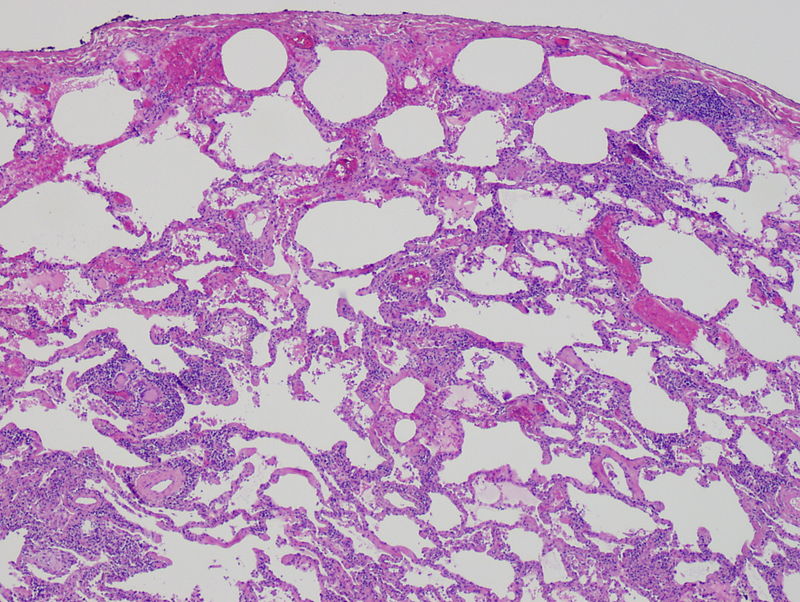

Idiopathic pulmonary fibrosis (IPF) is characterized by the scarring or fibrosis of lung interstitium.

Although the etiology is unknown, idiopathic pulmonary fibrosis (IPF) is likely related to cyclical lung injury as injured pneumocytes induce fibrosis.

Fibrosis on lung CT shows subpleural patches, which progress to diffuse fibrosis and eventually forms a ‘honeycomb’ pattern which is an indicator of end-stage pulmonary fibrosis.